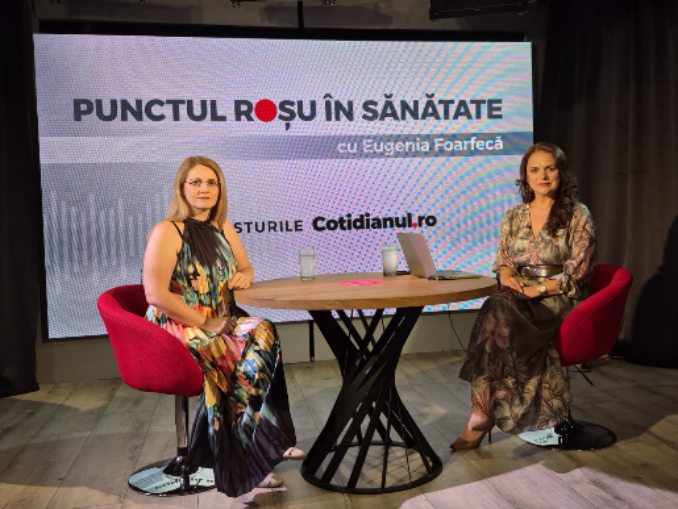

Invitat la Punctul Roșu în Sănătate, Prof. Univ. Dr. Petre Brătilă a vorbit despre cazurile de cancer de col uterin descoperite în stadii tardive, în România.

Reconstrucția unui vagin nou prin inginerie tisulară. 12 intervenții făcute cu grefă biologică, în România. Prof. Univ. Dr. Petre Brătilă: „La două luni pacienta poate avea contact sexual”. Tehnica oferă femeilor care au această malformație șansa de a avea o viață normală. Prof. Univ. Dr. Petre Brătilă este singurul din România care realizează procedura cu grefă biologică.

Punctul Roșu în Sănătate. Invitat: Raluca Buzea, coordonator programe de sănătate la Crucea Roșie

Prezent la Punctul Roșu în Sănătate medicul primar ORL Marian Stamate a vorbit dedpre cum vede personal situația rezidenților astăzi, în sistemul de sănătate. Rezidentul este ultima verigă într-un sistem feudal, veriga cea mai ușor de încărcat și cea mai greu de auzit instituțional, spune Marian Stamate. Le este teamă și sunt cazuri când sunt amenințați de coordonatorii de rezidențiat, mai spune medicul.